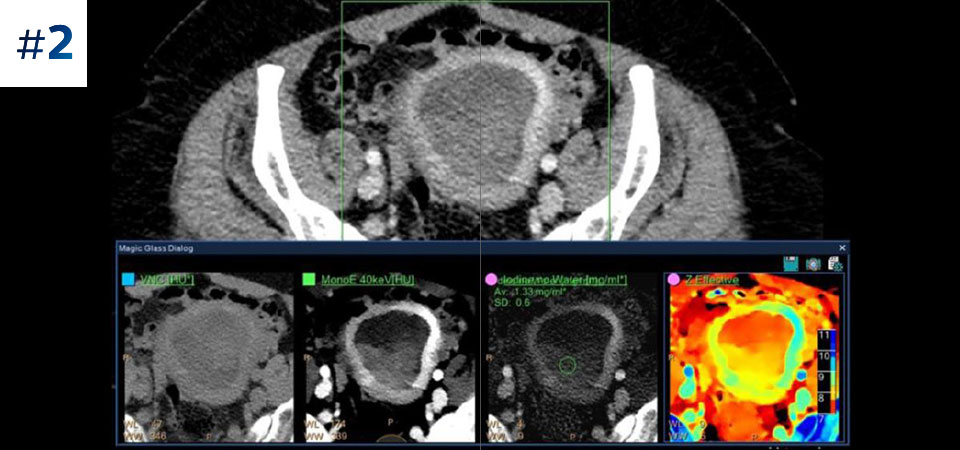

Moins d'examens complémentaires Une meilleure caractérisation et visualisation des tissus contribuent à réduire le besoin d'investigation complémentaire notamment lors de découvertes fortuites.

Allez plus loin que l'imagerie conventionnelle. Constatez par vous-même la pertinence de l'imagerie spectrale à la détection pour améliorer votre confiance diagnostique.